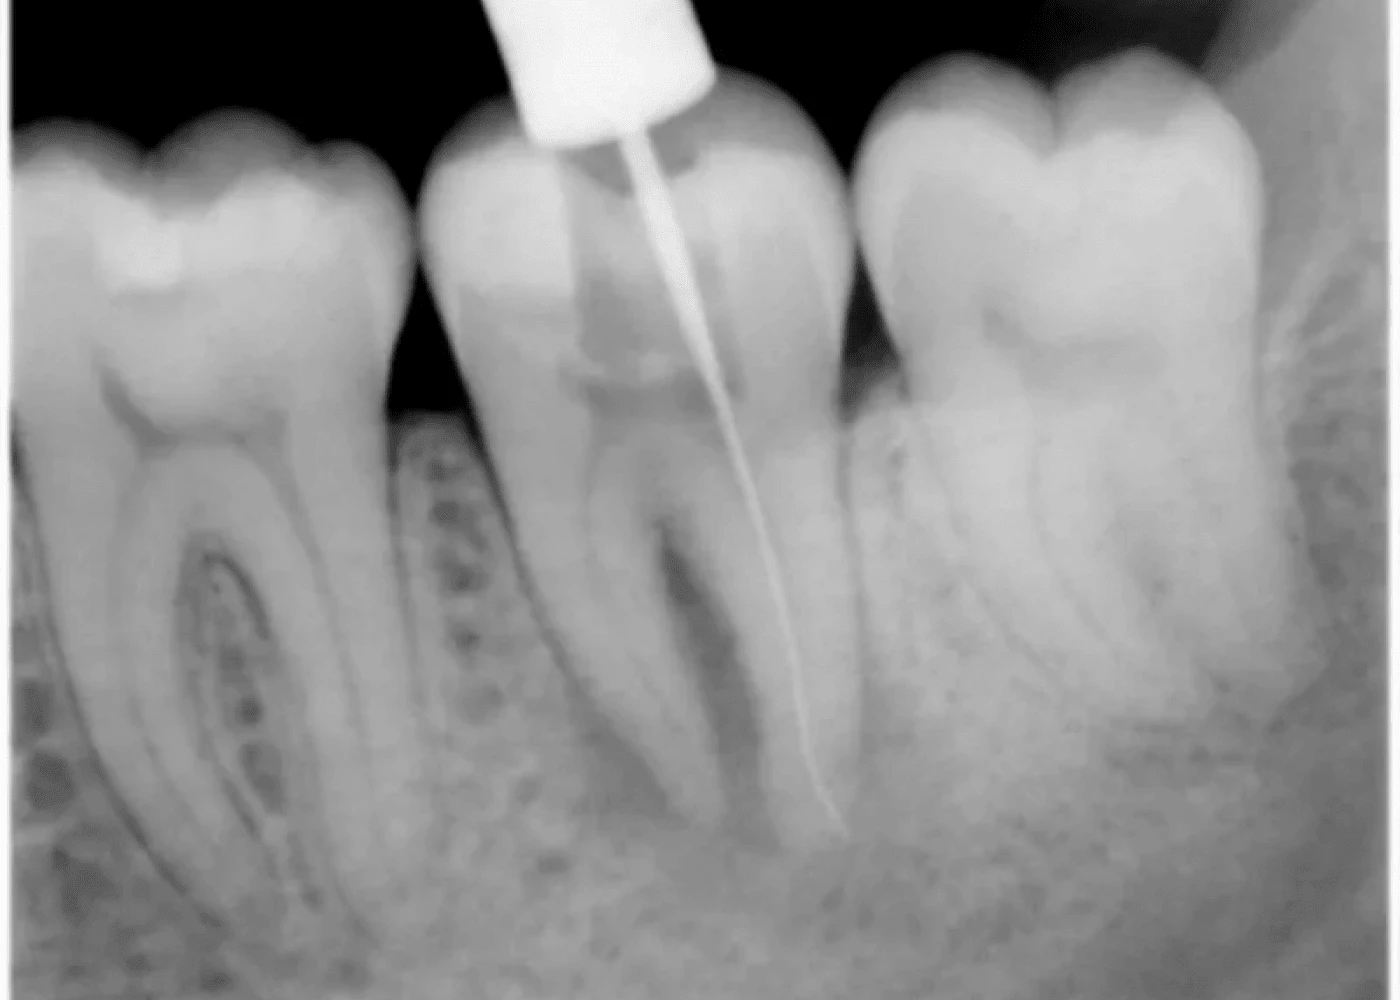

Рентген:

Рентген является одним из самых распространенных методов диагностики в стоматологии. Он позволяет визуализировать внутренние структуры зуба и окружающие ткани, включая корни и прилегающие кости. Рентген помогает обнаружить возможные очаги воспаления, остатки корневых каналов или пломбировочных материалов, которые могли стать причиной боли.

Апекслокатор используется для точного определения длины корневого канала. Это устройство позволяет избежать ошибок при пломбировании канала и обеспечивает более точное лечение. Неправильно обработанный или неполный корневой канал может быть источником проблемы и вызывать боль.